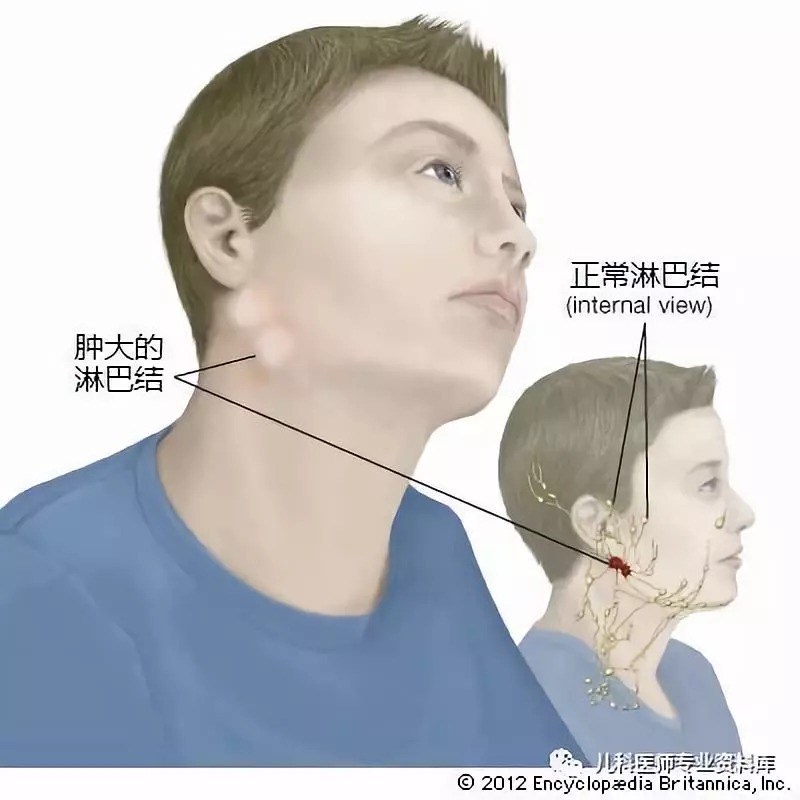

颈部淋巴结肿大_图片_互动百科

双下颌淋巴结肿大,最大的约有2*1cm大小,无痛,质中,表面光滑,活动性良好。